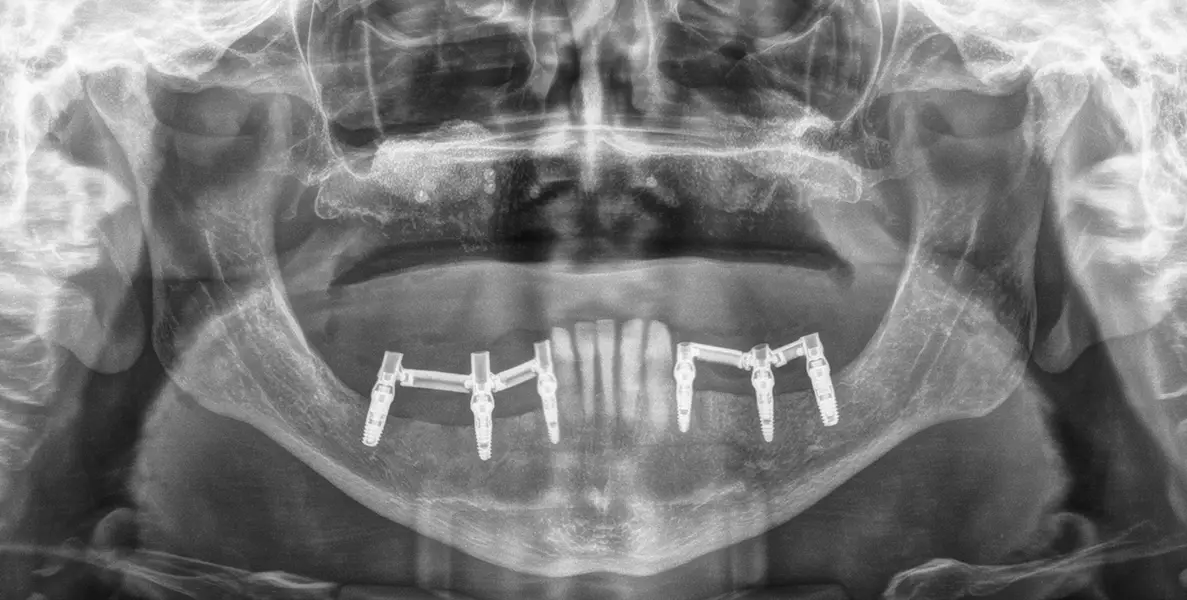

En las figuras 4-28 se muestra uno de los casos incluidos en el estudio, donde ambos sectores posteriores mandibulares fueron rehabilitados con este tipo de implantes.

Figuras 16 y 17. Implantes colocados tras la cirugía.

Figura 18. Radiografía de la carga inmediata de 4 de los 5 implantes de diámetro reducido. Estos implantes son ferulizados a otros de mayor diámetro para la confección de la prótesis y esta se construye sobre transepiteliales, atornillada con barras articuladas horas después de la cirugía.

Figura 23. Radiografía con la prótesis final en el momento de su colocación, 6 meses de la carga inicial. Como vemos la prótesis final se divide en tres sectores para lograr un mejor comportamiento biomecánico del conjunto.

Figura 28. Radiografía panorámica de control dos años después, observándose la estabilidad lograda y el mantenimiento del hueso crestal en todos los implantes.